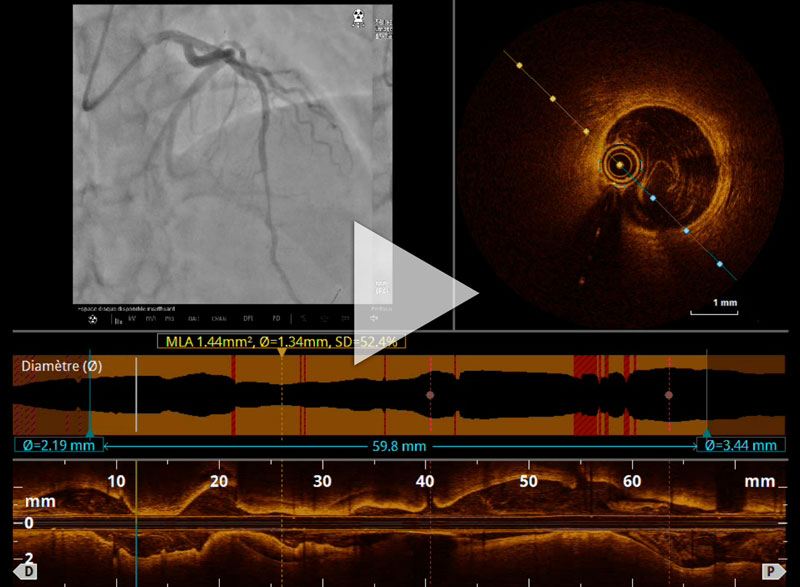

Figure 4A : Séquence d’imagerie endocoronaire par OCT

Figure 4B : Vidéo de séquence d’imagerie endocoronaire par OCT

L’imagerie endocoronaire n’est pas obligatoire pour le diagnostic de dissection coronaire spontanée. Elle peut s’avérer utile lorsqu’un doute diagnostic persiste, ou pour guider le traitement interventionnel. Très souvent, l’OCT (Optical Coherence Tomography) est préférée à l’IVUS (Intravascular Ultrasound) pour sa haute résolution spatiale (résolution axiale de 15mm). Le choix de notre équipe a été de réaliser une imagerie endocoronaire par OCT en phase aiguë.

Sur cet OCT, on peut visualiser l’hématome disséquant avec aspect en croissant de la fausse lumière. Ici, la fausse lumière, composée d’hématome intramural, enveloppe et comprime la vraie lumière. Il n’y a pas de porte d’entrée retrouvée sur cet examen. À noter qu’en amont et en aval de cette zone, on retrouve une artère sans plaque athéromateuse avec ses trois tuniques bien individualisables (intima, media et adventice).